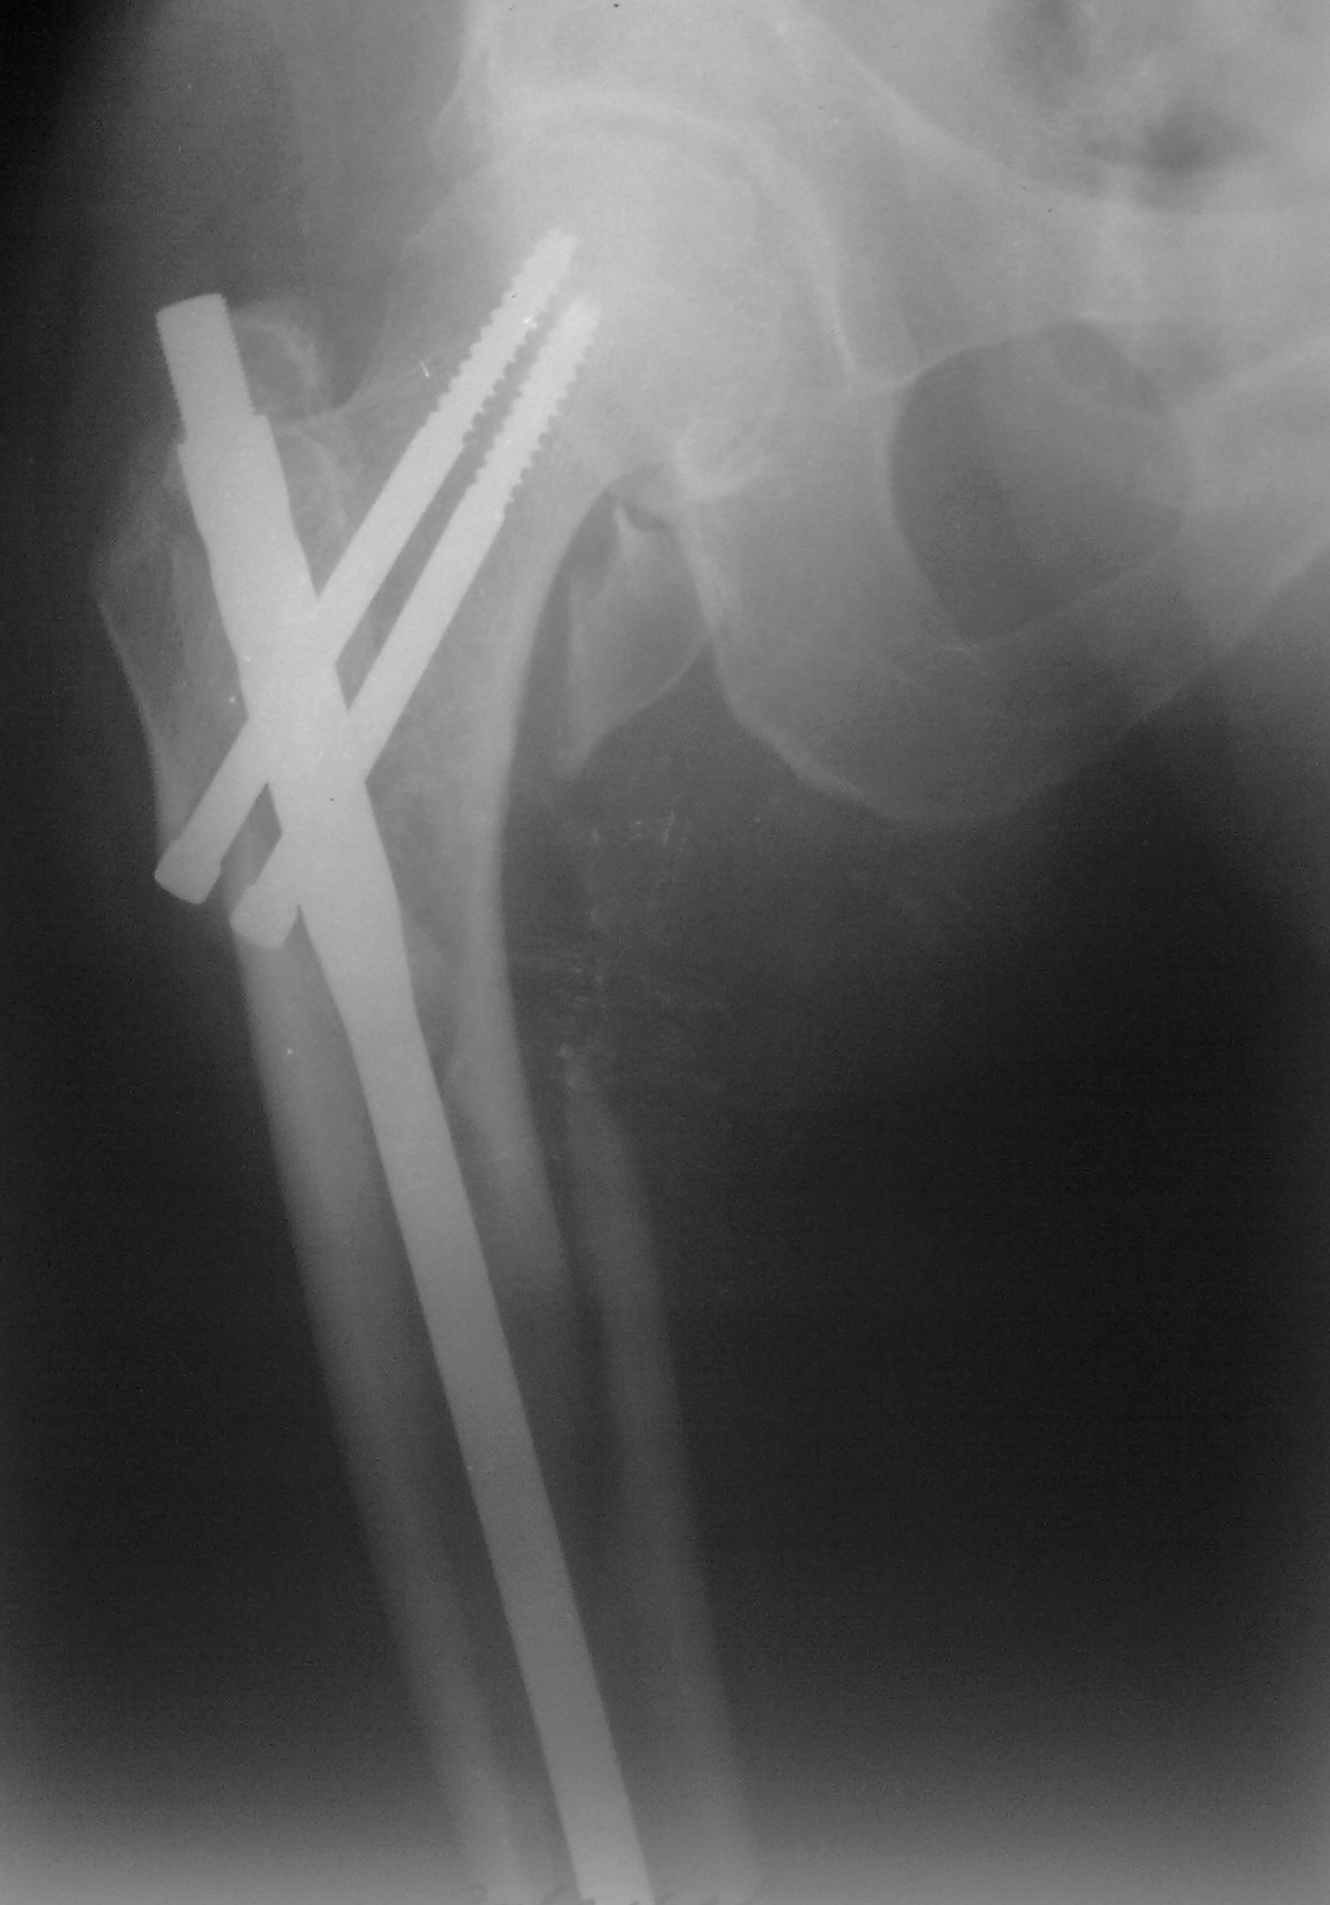

Пациент 83 года. Реконструктивный бедренный стержень Chm

При многооскольчатых переломах стержень может "выпасть" кзади под весом кондуктора и своим, даже если поначалу он вводился правильно. Чтобы эту неприятность предупредить, стоит ввести спицу по оси шейки бедра вдоль ее задней стенки, типа как на картинке. Если стержень кпереди от этой спицы вводить, то он за нее не провалится.